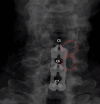

Figure 2. Postoperative X-ray after C5-7 ACDF with total uncinatectomies

The image demonstrates good placement of hardware, with lucency in the C5-6 and C6-7 foramen (red circles) demonstrating complete removal of the uncinate and total decompression of the cervical roots ACDF: anterior discectomy and fusion